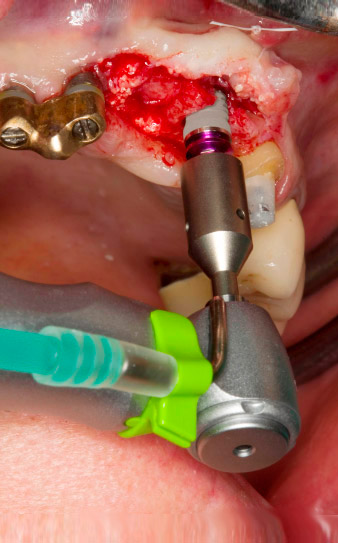

Нарязване с винт с обратен наконечник WS-75 L

Фиг. 3: Нарязване с винт с обратен наконечник WS-75 L със съотношение 20:1 (програма P4). Високият въртящ момент на Implantmed, хексагоновата система на цангата за надеждно предаване на мощноста и автоматичното обръщане на посоката на въртене, когато съпротивлението стане твърде голямо, са особено полезни в този случай.